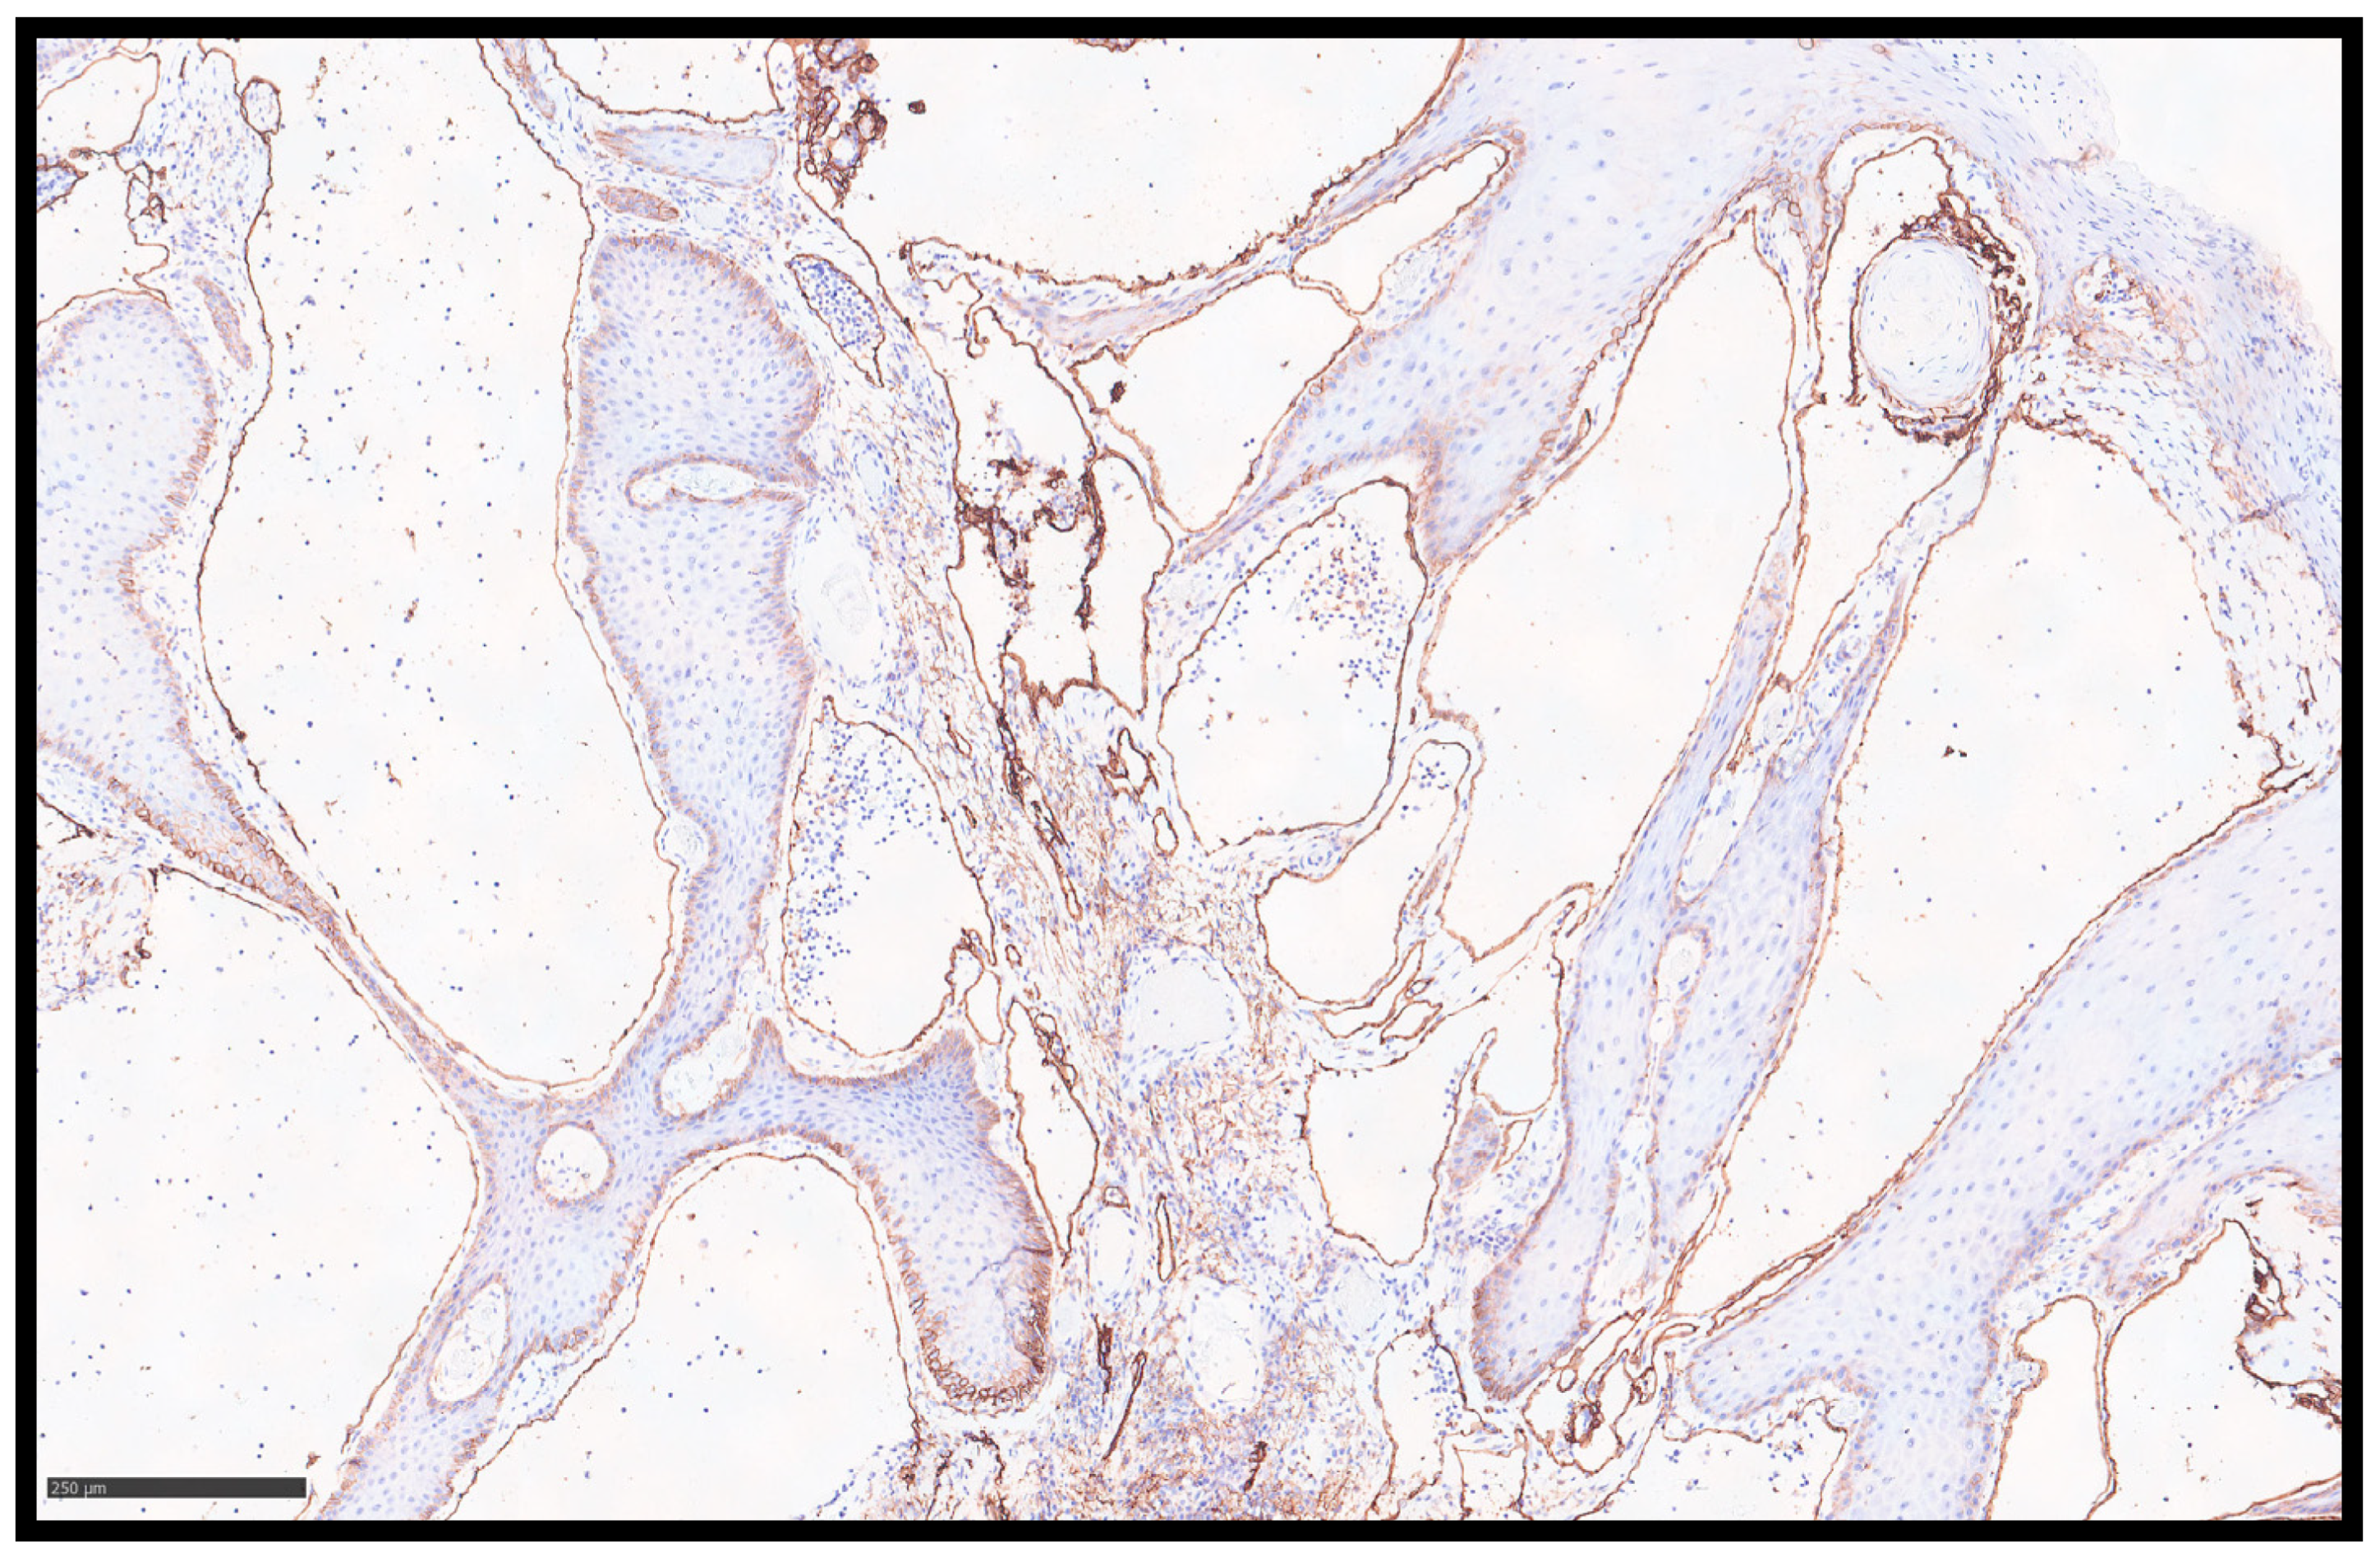

Histopathological examination showed a papillomatous lesion characterized by hyperkeratosis, focal erosion, and dilated vessels lined by flat endothelial cells without atypia containing lymphocytes and serum (Figure 2A–C); furthermore, the lymphatic nature of the vessels was confirmed by immunohistochemical reaction with Podoplanin (D2-40) (Figure 3).

Figure 3. An immunohistochemical investigation with anti-D2-40 antibody showing the endothelial layer of the lymphatic vessels (immunohistochemistry, original magnification 10×).